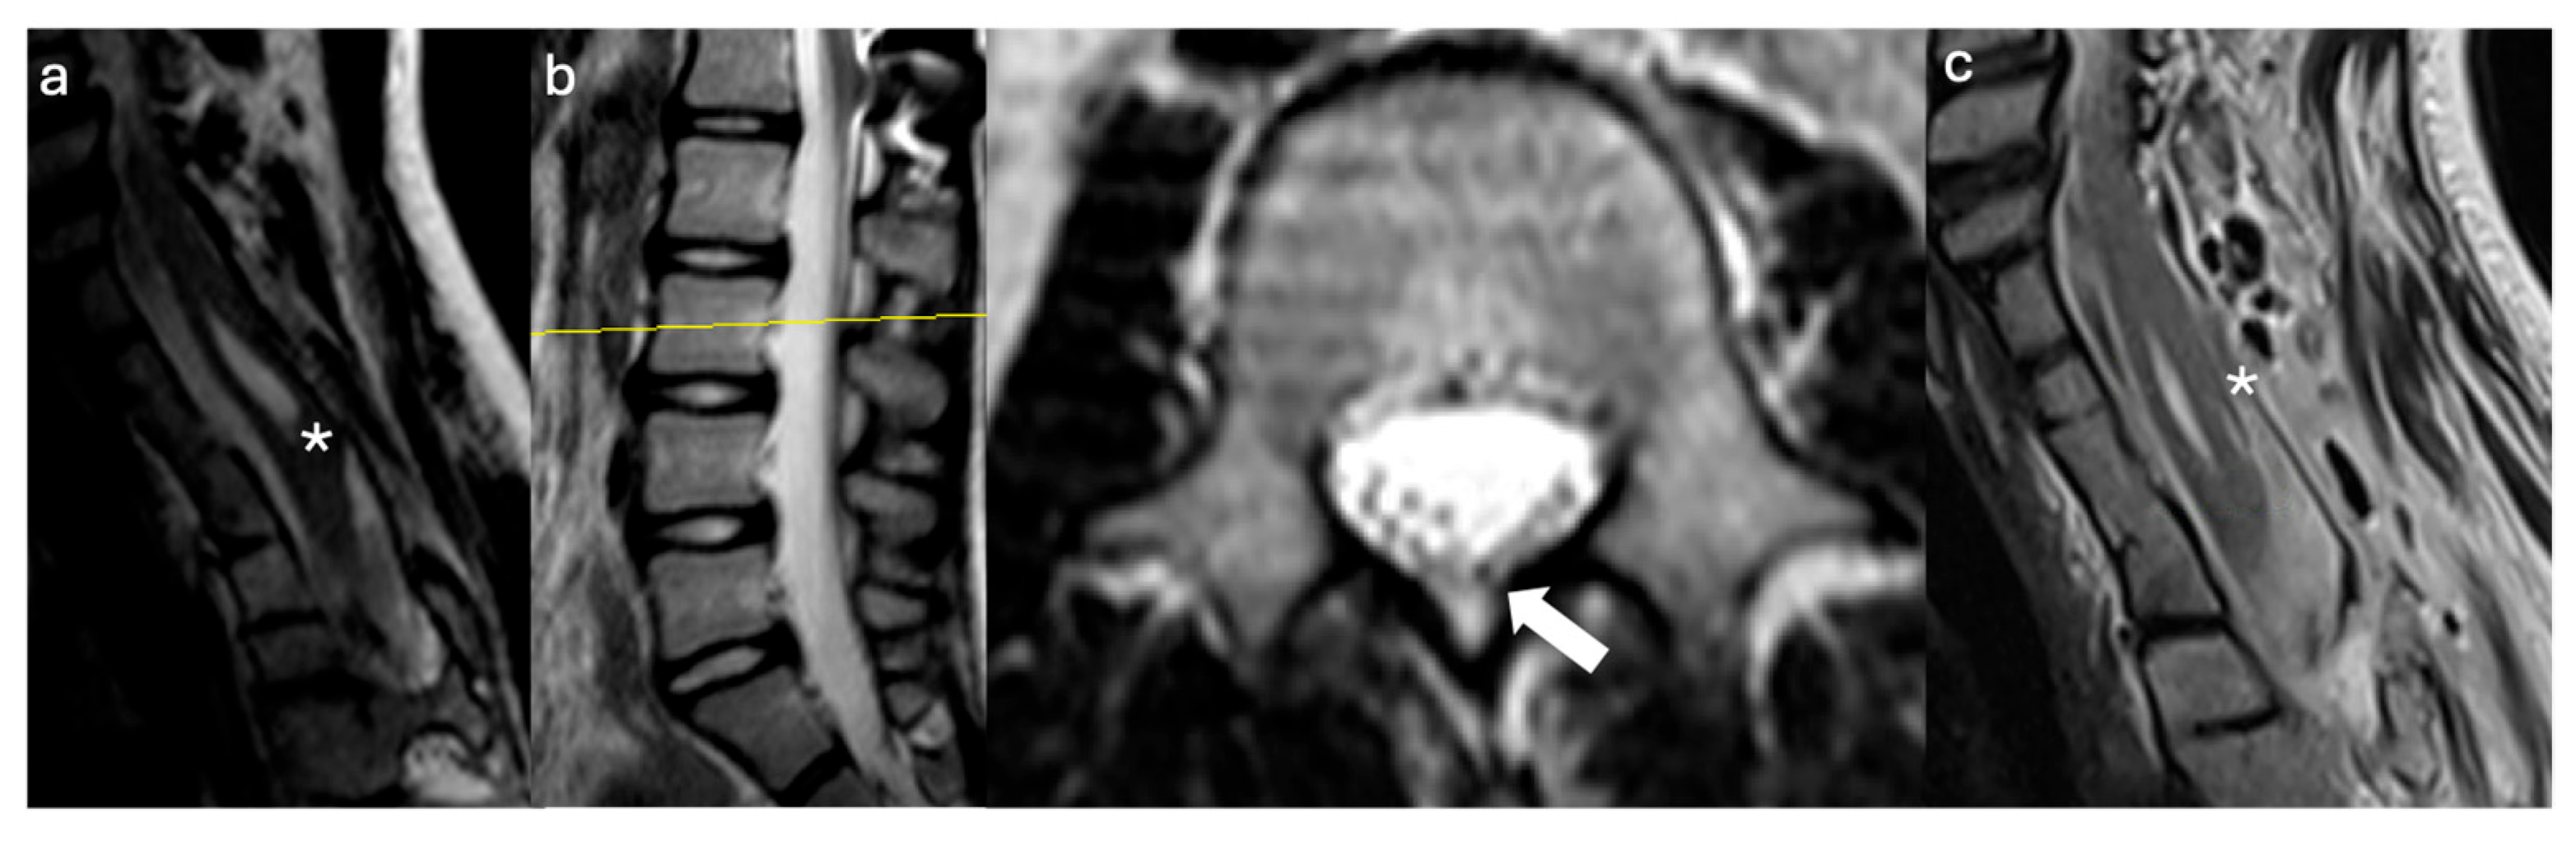

3.2.1. Case #1

3.2.2. Case #2

3.2.3. Case #3

3.2.4. Case #4

3.2.5. Case #5